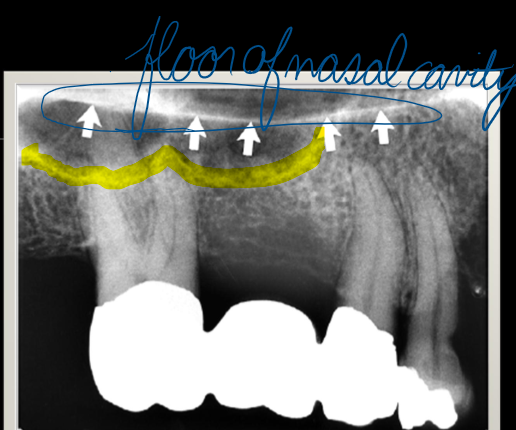

hard palate

highlight

anterior nasal spine